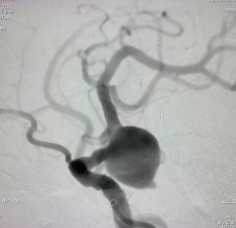

生死时速!造影剂过敏险丧命,市一专家“脱敏”手术破解颅内“不定时炸弹”

发布时间: 2025-10-27